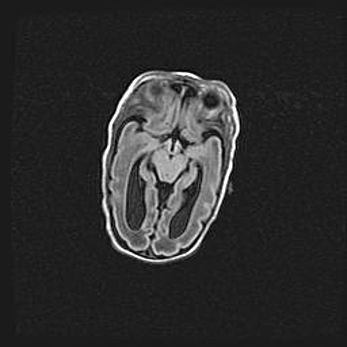

Лейкомаляция с кистозно-глиозной дегенерацией головного мозга.

Возраст: 2 месяца 25 дней

Вес: 6400 г

Окружность головы: 40 см

Срок гестации: 41 неделя

Лейкомаляцию относят к ишемически-гипоксическим повреждениям головного мозга, диагностируемым у новорожденных. При лейкомаляции в головном мозге обнаруживают очаги некроза, возникшие после тяжелой гипоксии и нарушения кровотока. В процессе морфогенеза очаги проходят три стадии: 1) развития некроза, 2) резорбции и 3) формирования глиозного рубца или кисты. Перивентрикулярная лейкомаляция (ПЛ) встречается примерно в 12% случаев среди новорожденных, обычно – у недоношенных детей, причем, частота ее зависит от массы, с которой младенец появился на свет. Наибольшее число малышей страдает лейкомаляцией, если масса при рождении 1500-2500 г.